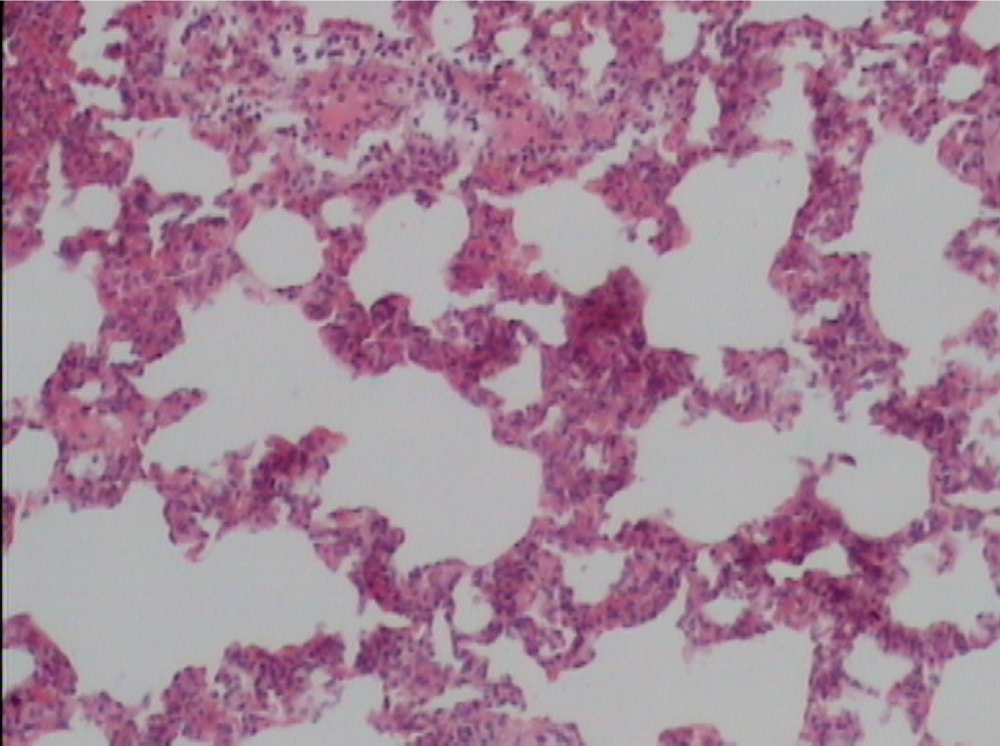

Supplementation of probiotics will effectively prevent neutrophil infiltration of the lung and also reduce the subsequent tissue destruction, as demonstrated in studies with inflammation induced by cecal ligation and puncture (CLP). A synbiotic formulation, Synbiotic 2000 Forte (see further below), was administered orally before the induced trauma and effectively prevented both neutrophil accumulation and tissue destruction in the lungs [50]. Most interestingly, these effects were obtained also when the LAB of the composition were injected subcutaneously (Figure 1,Figure 2,Figure 3) [51].

The average neutrophil count in the lungs (average of five fields) was: mixture of LAB and bioactive fibers 9.00 ± 0.44 (1), only LAB 8.40 ± 0.42 (2), only bioactive fibers 31.20 ± 0.98 (3), placebo (non-fermentable fiber) 51.10 ± 0.70 (4). The reduction of inflammation by the treatment was also demonstrated by significant reductions in myeloperoxidase (MPO), malondialdehyde (MDA), and nitric oxide (NO): MPO being 25.62 ± 2.19 (1), 26.75 ± 2.61 (2), 56.59 ± 1.73 (3), and 145.53 ± 7.53 (4) respectively (resp.), MDA 0.22 ± 1.31 (1), 0.28 ± 3.55 (2), 0.48 ± 5.32 (3) and 0.67 ± 2.94 (4) resp. and NO 17.16 ± 2.03 (1), 18.91 ± 2.24 (2), 47.71 ± 3.20 (3) and 66.22 ± 5.92 (4) resp.—all differences being statistically significant (>0.05).

Figure 1.

Control group.